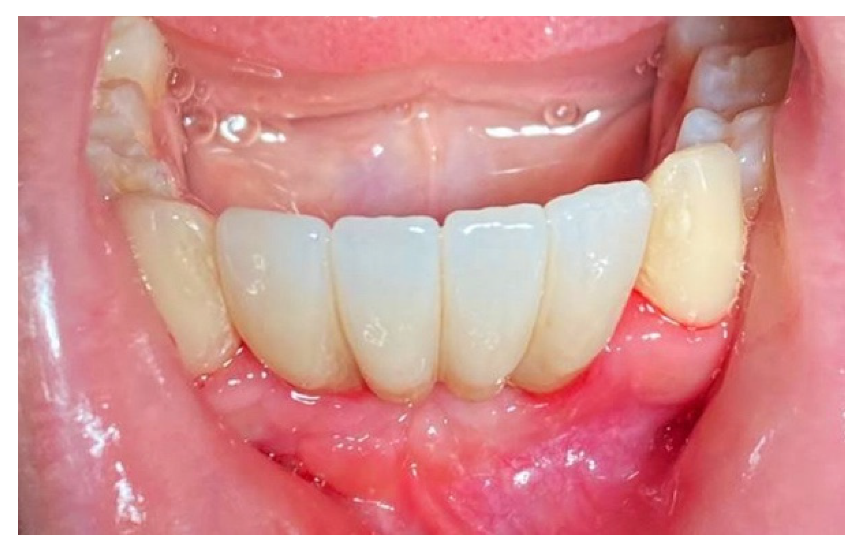

The patient was prosthetically rehabilitated with additional implants positioned in 4.2 and 3.2 (post-extractive). In this case, we also noted how soft tissues surrounding the regenerated site were mature and stable (Figure 18).

Figure 18.

Prosthetic finalization of the case and mucose quality.

The surgery protocol was the same as described in the previous case (Figure 11a–e). The extraction of teeth and the simultaneous insertion of the implants was performed in the same session (Figure 11a). The enriched clot (1 g beta-tricalcium phosphate for every 5 mL of clot) was protected by the shaped foil fixed with screws (Figure 11b) and its successive removal was at six months (Figure 11c). A further six months were necessary for soft tissue maturation (Figure 11d,e). In this case, the flap of keratinized mucosa, indicated by the white arrow in Figure 11c–e, contributed to the stability of the keratinized mucosa. At the follow-up, the gingival tissue was adequately matured, avoiding further graft of soft tissue (Figure 12).

Figure 12.